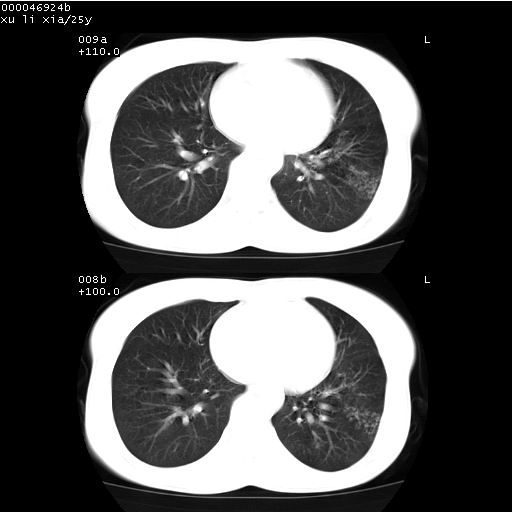

患者 女,25岁。因“左侧卵巢肿瘤”术前胸片偶然发现两肺病变。平素无明显不适,无呼吸系统症状及体征,无传染病史。

cr x线胸片提示:两肺感染性病变(结核可能性大)。

胸部ct轴位平扫(层厚10mm,螺距1.5,重建间隔10mm),图像如下:

(注:上级医院会诊胸部ct片——考虑为肺部真菌感染。)

病灶呈地图样分布于肺外围,与正常组织分界清晰+弥漫性磨玻璃影中见小叶间隔增厚呈碎石路样表现+年轻女性,无明显临床症状=肺泡蛋白沉积症?

双肺上叶可见节段性渗出性病变,可见树芽征像,左肺下叶背段可见结节影。

病灶呈离心性分布,以两上肺多见,远离肺血管纹理,有部分肺间质条索影,病人症状轻微,考虑结节病。